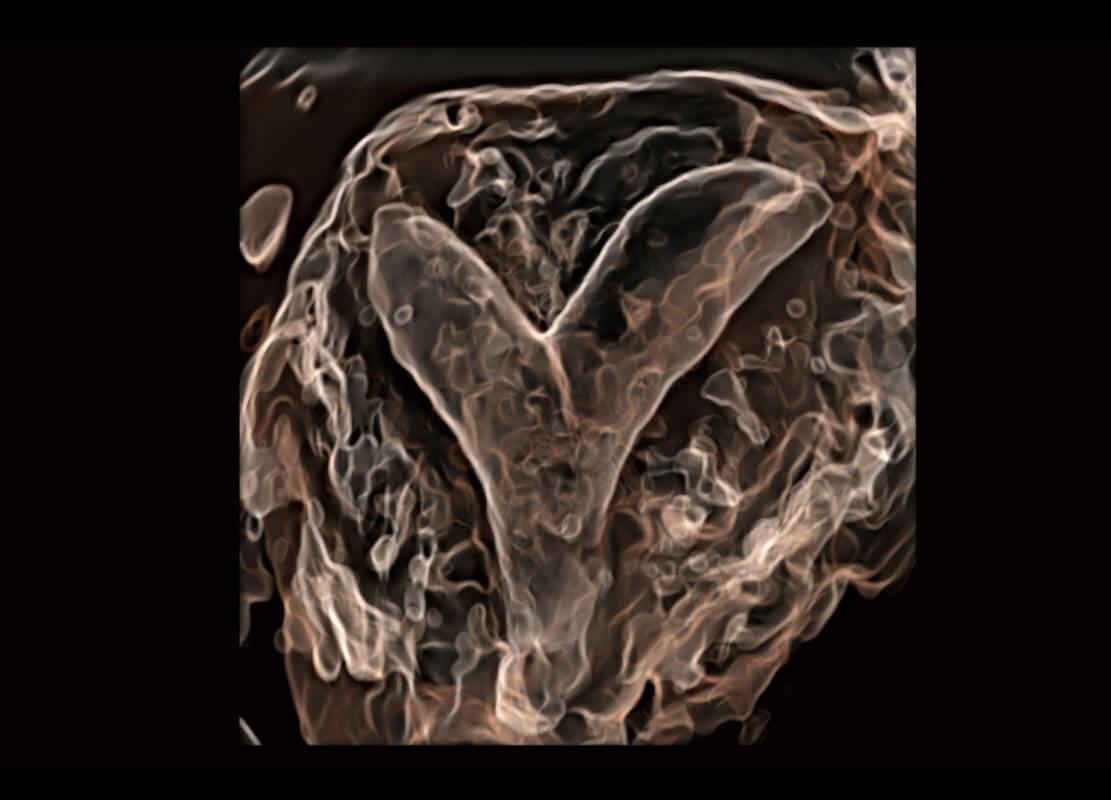

腔內(nèi)三維-光影成像

P60優(yōu)異的圖像質(zhì)量搭載專(zhuān)科探頭,在婦科基礎(chǔ)疾病的診斷、卵泡生長(zhǎng)的監(jiān)測(cè)、輸卵管通暢情況的判別等方面為您提供生殖應(yīng)用方案。